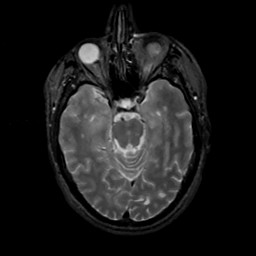

MR Study #10, April 28, 1991 -- Slice #18

[Home][Help][Clinical][Tour 1][Tour 2] Slice 18